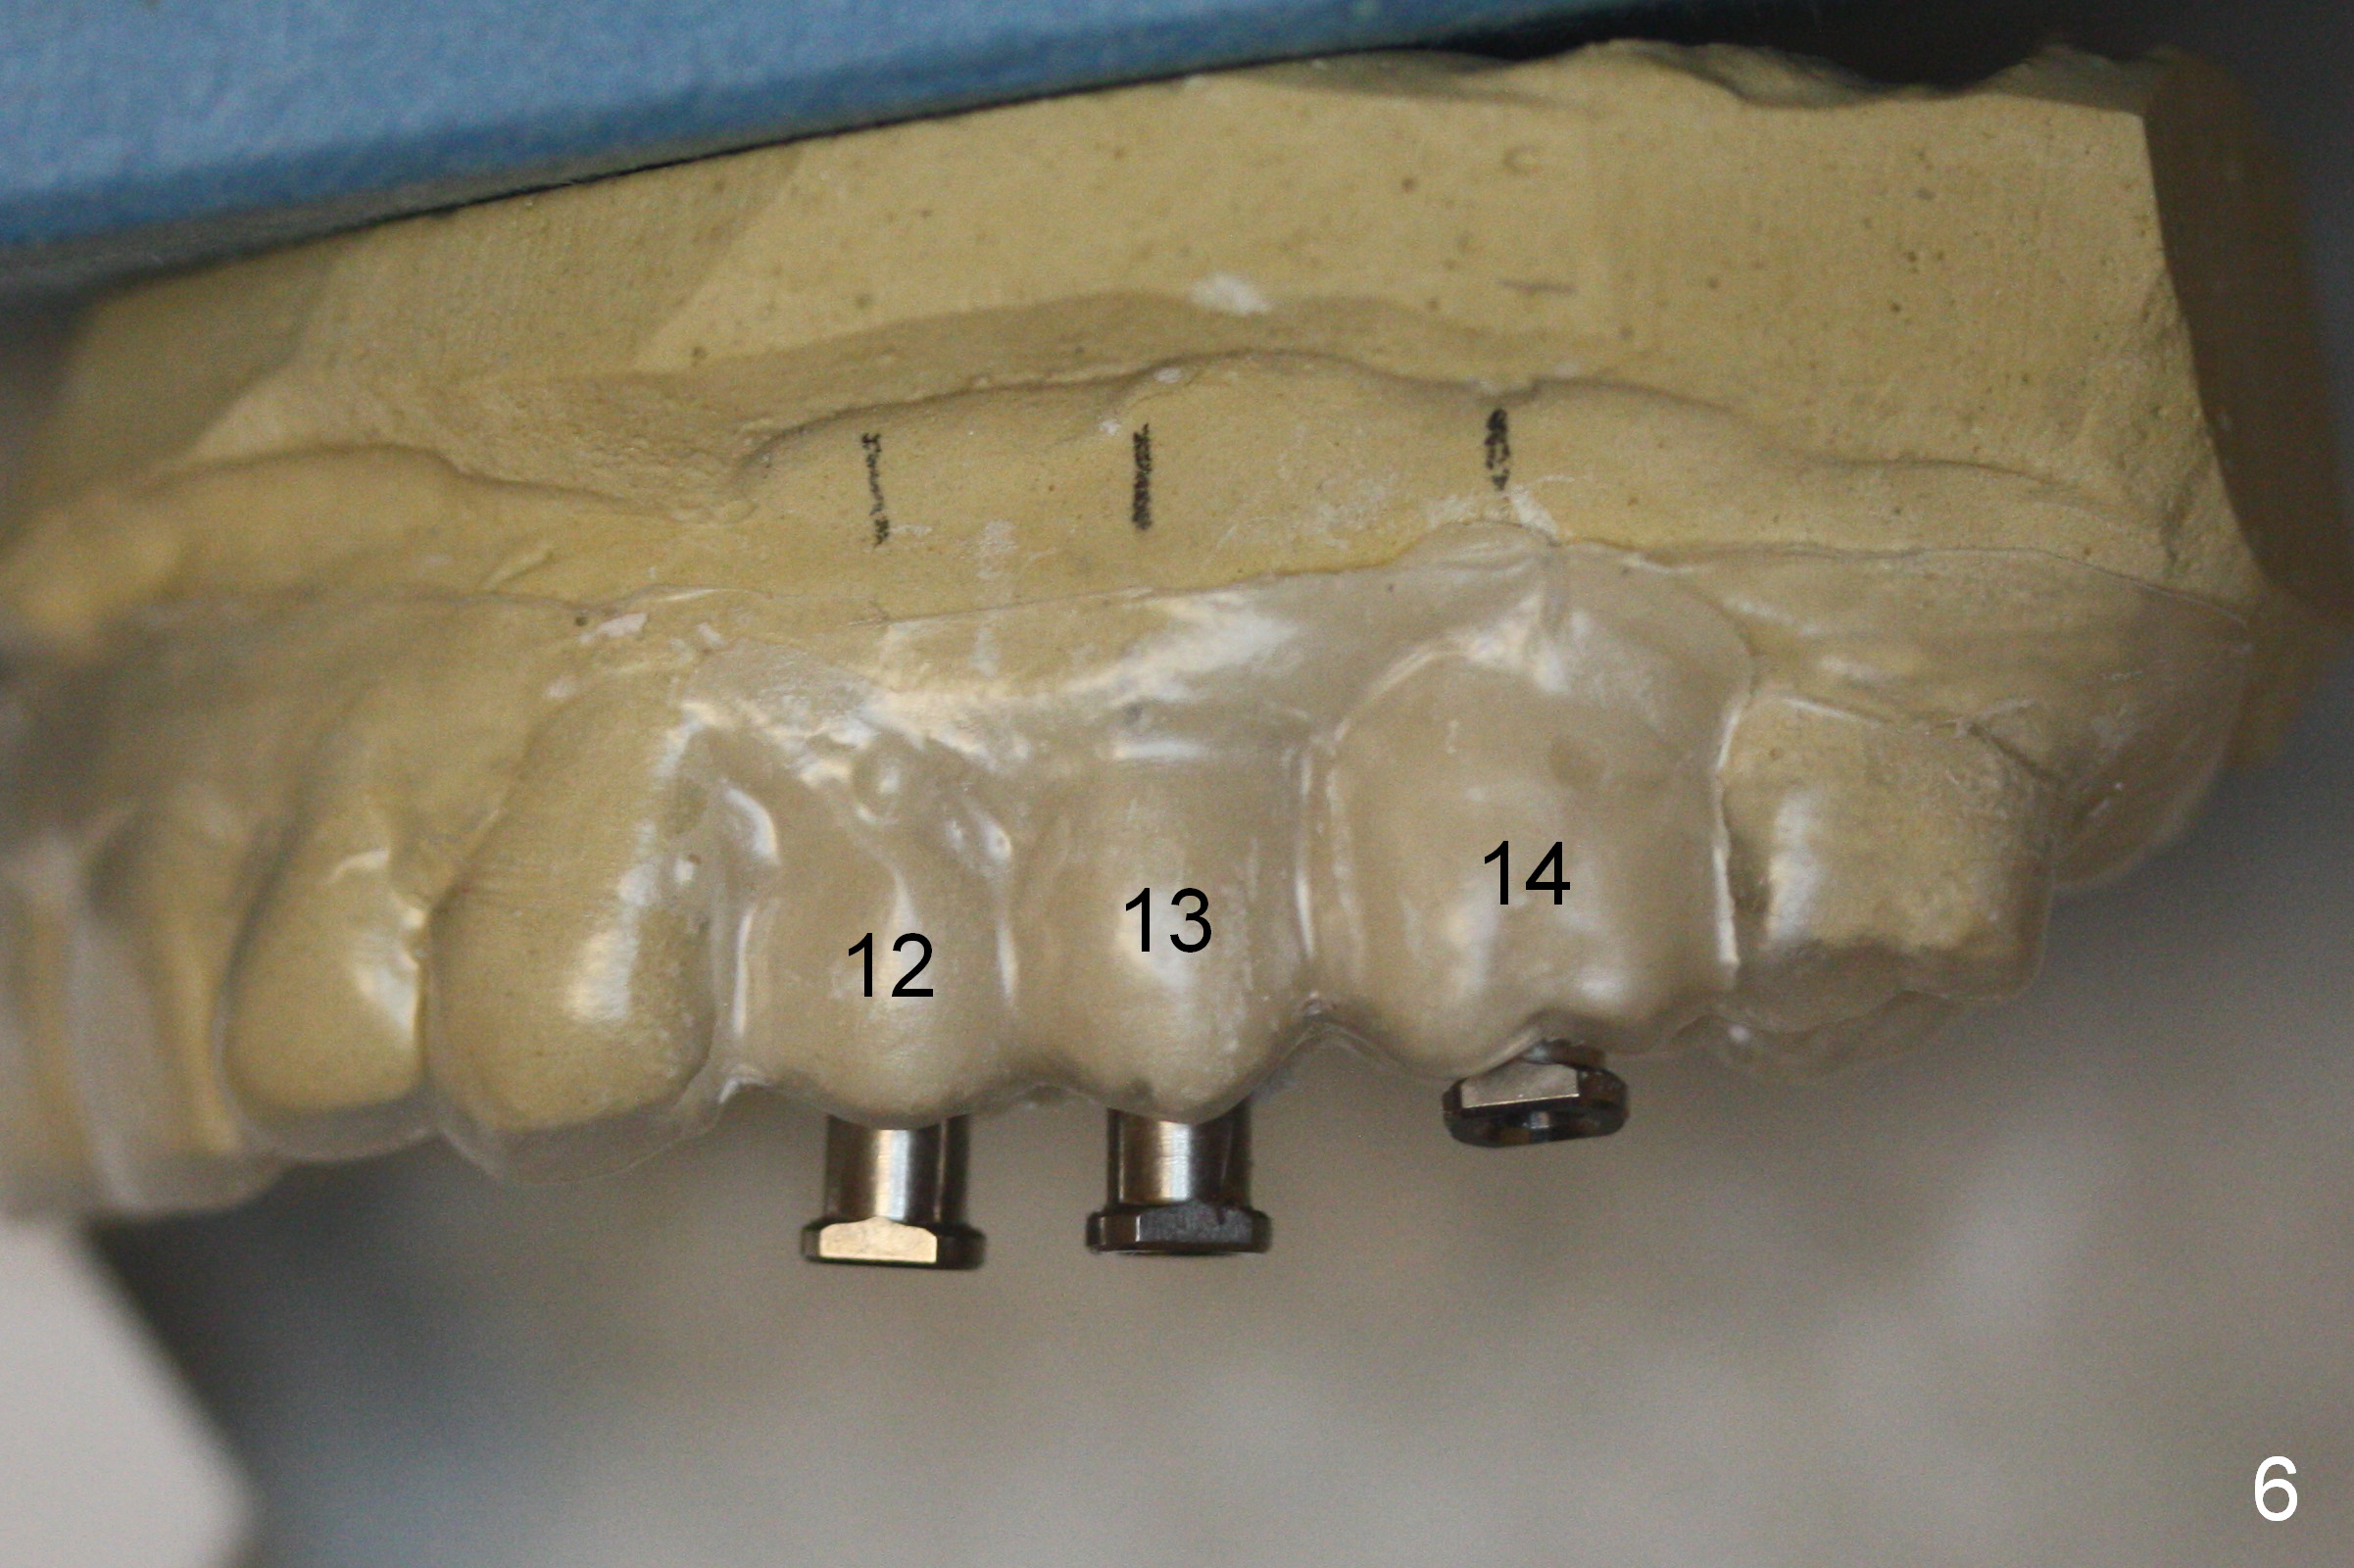

Three implants will be placed in the upper left posterior sextant (Fig.1-4). Without incision, place a surgical stent with trajectory tubes in place. Start osteotomy through the metal tubes (Fig.5,6) with a 2 mm pilot drill (SM) with drill extension if necessary. Palpate the buccal plate while drilling. Insert parallel pins for PA. According to the size of keratinized gingival band in the edentulous area, use either a 4 mm tissue punch or #15 scalpel for access. This way favors the trajectory over the diameter and length of the implants.